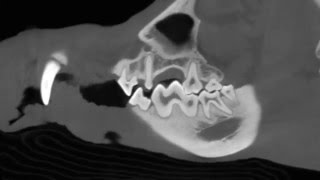

The Vimago, The Technology Behind Mpi, In The News Mobile Pet Imaging — 1:49 · 10 yıl önce · 80 görüntüleme Video Olarak İndir Mp3 Olarak İndir Vimago Technology Behind News